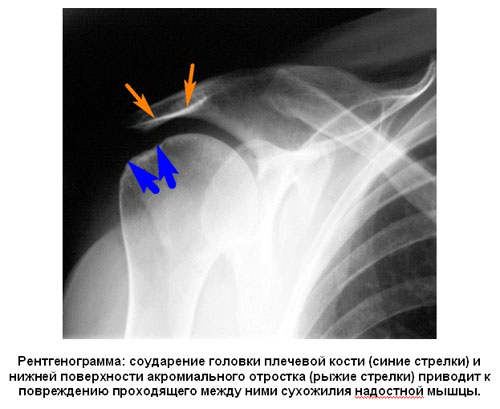

Обязательно выполнение рентгенографии, на которой при разрывах сухожилий вращательной манжеты можно обнаружить характерные признаки на нижней поверхности акромиального отростка - так называемый субхондральный склероз. Он образуется как защитная реакция кости от многократного соударения головки плечевой кости и нижней поверхности акромиона (импинджемент синдром), и эти соударения приводят к повреждению сухожилий вращательной манжеты, вызывают их тенопатию, и, в конечном итоге, разрыв. Конечно же, отсутствие на рентгенограмме этих признаков не говорит о том, что сухожилия вращательной манжеты не повреждены, но наличие этих рентгенологических признаков с высокой долей вероятности говорит о проблемах с сухожилиями ращательной манжеты. На рентгенограмме важно оценить и акромиально-ключичное сочленение: артрит этого сустава может служить причиной похожих болей.